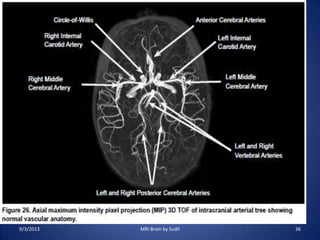

MR Angiography (MRA)

• Time-of-flight (TOF) or Inflow

angiography, uses a short echo time

and flow compensation to make

flowing blood much brighter than

stationary tissue.

• As flowing blood enters the area

being imaged it has seen a limited

number of excitation pulses so it is

not saturated, this gives it a much

higher signal than the saturated

• Indications :

– Evaluation of cerebral arteries in cases of stroke,

subarachnoid and intracerebral hemorrhage,

trauma, AVM, suspected or known aneurysm etc.

• Sequence:

– 3D TOF for circle of willis in the axial plane

– 3D TOF for vertebrobasilar system in axial plane

– For AVM, additional sequences needed are

– 3D TOF through region of interest

9/3/2013 MRI Brain by Sudil 34